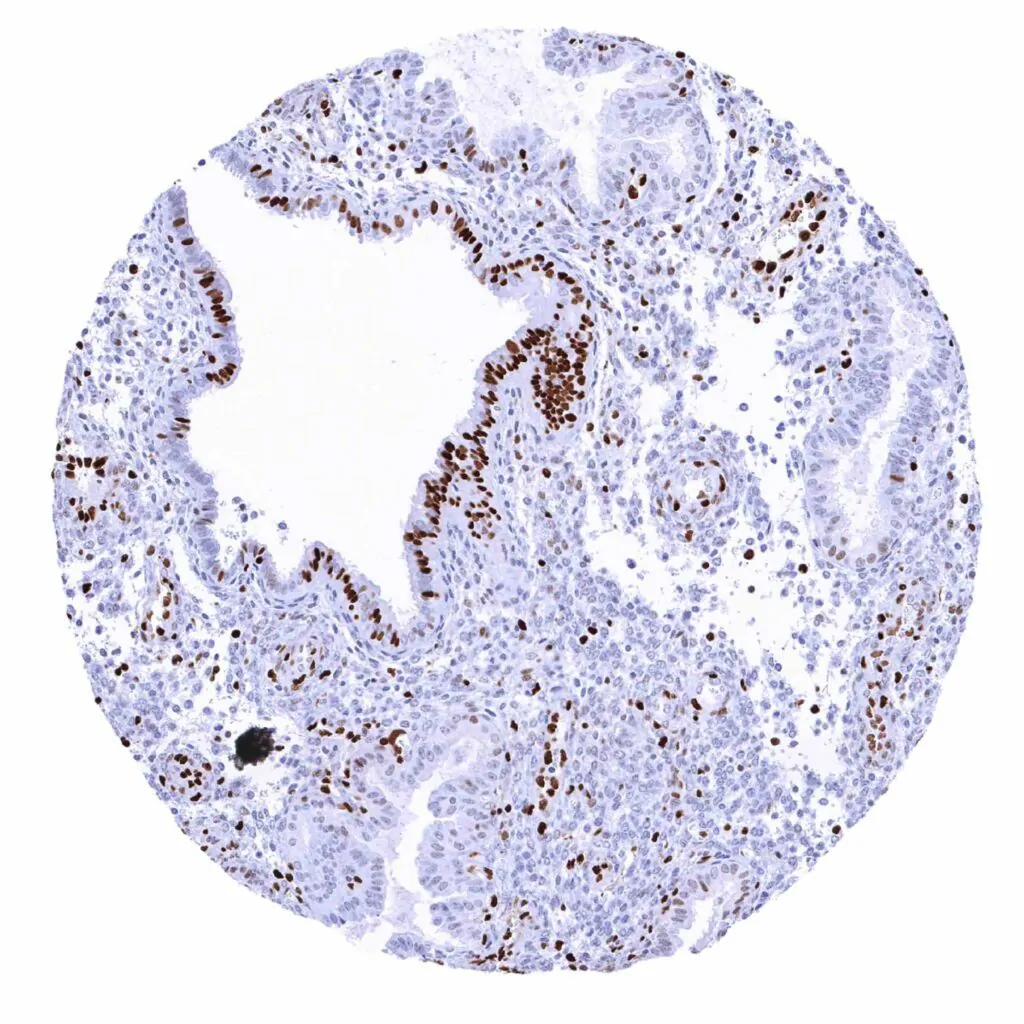

Colon descendens, mucosa – MCM2 staining predominates in epithelial cells of the crypts

Rectum, mucosa – The strongest MCM2 staining occurs in the deepest epithelial cells of the crypts

Duodenum, mucosa – MCM2 staining predominates in epithelial cells of the crypts

Ileum, mucosa – MCM2 staining predominates in epithelial cells of the crypts

Appendix, mucosa – MCM2 staining predominates in in epithelial cells of the crypts. Some lymphocytes are also positive